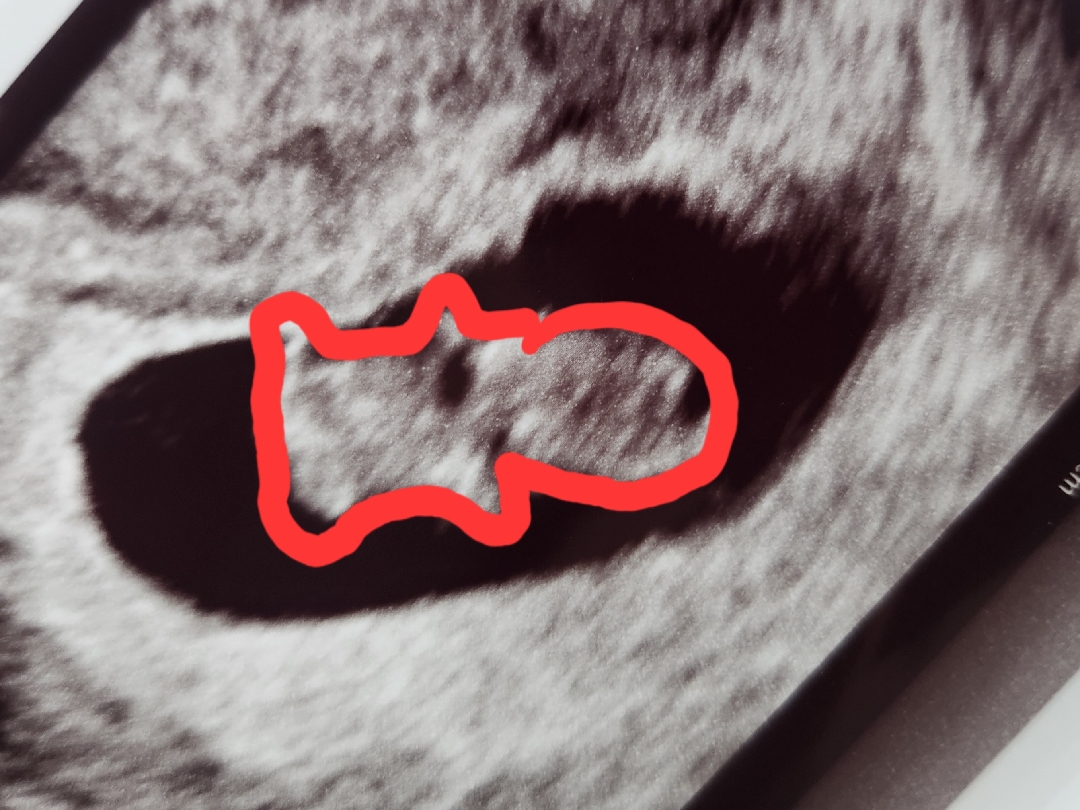

젤리곰 보고왔어용

꼬물꼬물 움직이는게 너무 귀엽고 신기하고...잘크고있어줘서 너무너무 감사하고 ㅎㅎ진짜 너무 귀엽네요 2cm라니...